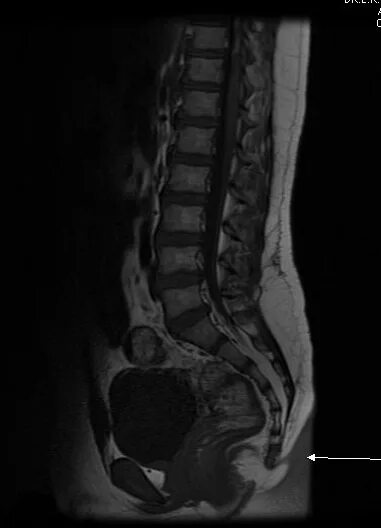

Смещение копчика